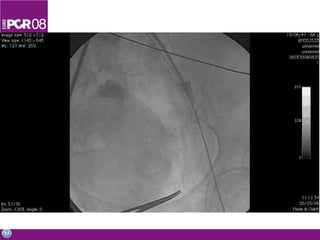

Cath lab Vascularaccess Catheterization Angiography PTCA Non coronary interventions Material inventory Simple diagnostics done in the OR

• #48 Cath lab is the best set-up to learn basic and advanced catheter skills. I have learned the many aspects and the importance of a good vascular access, and performed some basic skills including catheterization and angiography, while I assisted in PTCA and non coronary interventions. The cath lab is an unique opportunity to learn catheter management, and to be exposed to the large inventory of material and devices. In a second step, we run some simple diagnostic procedures in the OR to assess feasigbility and reliability of such new setup. Here you see an angio performed in the OR.